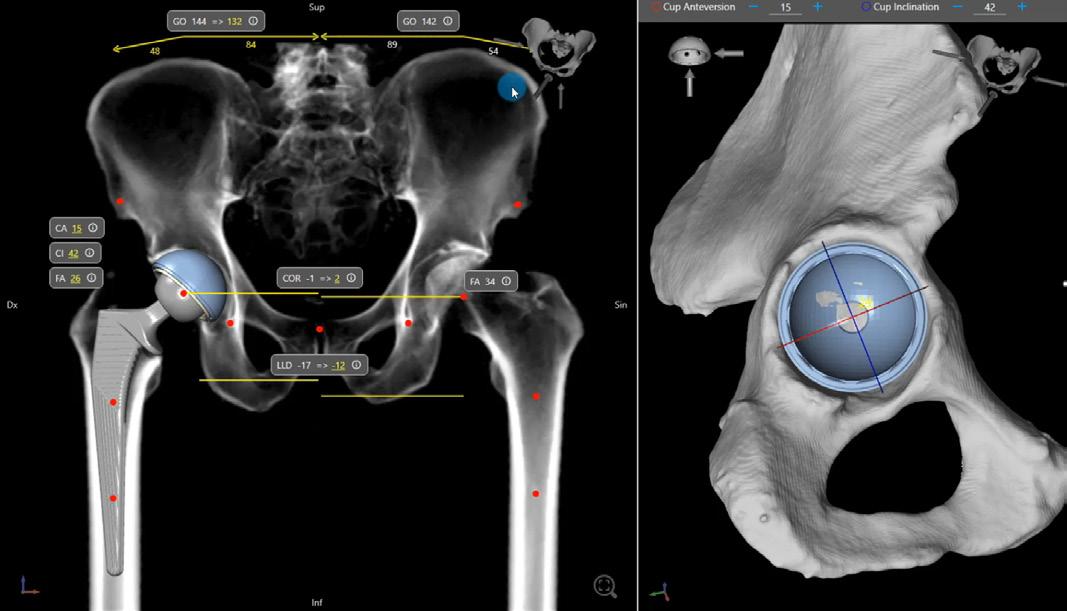

Under ledning av Jörg Schilcher, US Linköping och Peter Wildeman, Örebro genomfördes en kurs i höftrevision i samarbete med Link. Deltagarna fick träna på att hantera rekonstruktionsprotes på femur och acetabulum. En uppskattad del av kursen var de garagebyggda acetabulum-modellerna i plast utblandat med träfibrer. Mod ellerna var baserade på riktiga patienter och tack vare den speciella material sammansättningen återskapades en autentisk situation.